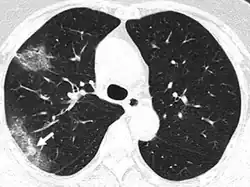

In COVID-19, the arterial and general tissue oxygen levels can drop without any initial warning. The chest x-ray may show diffuse pneumonia. Cases of silent hypoxia with COVID-19 have been reported for patients who did not experience shortness of breath or coughing until their oxygen levels had depressed to such a degree that they were at risk of acute respiratory distress (ARDS) and organ failure.[22] In a New York Times opinion piece (April 20, 2020), emergency room doctor Richard Levitan reported: "A vast majority of Covid pneumonia patients I met had remarkably low oxygen saturations at triage—seemingly incompatible with life—but they were using their cellphones as we put them on monitors."[22]